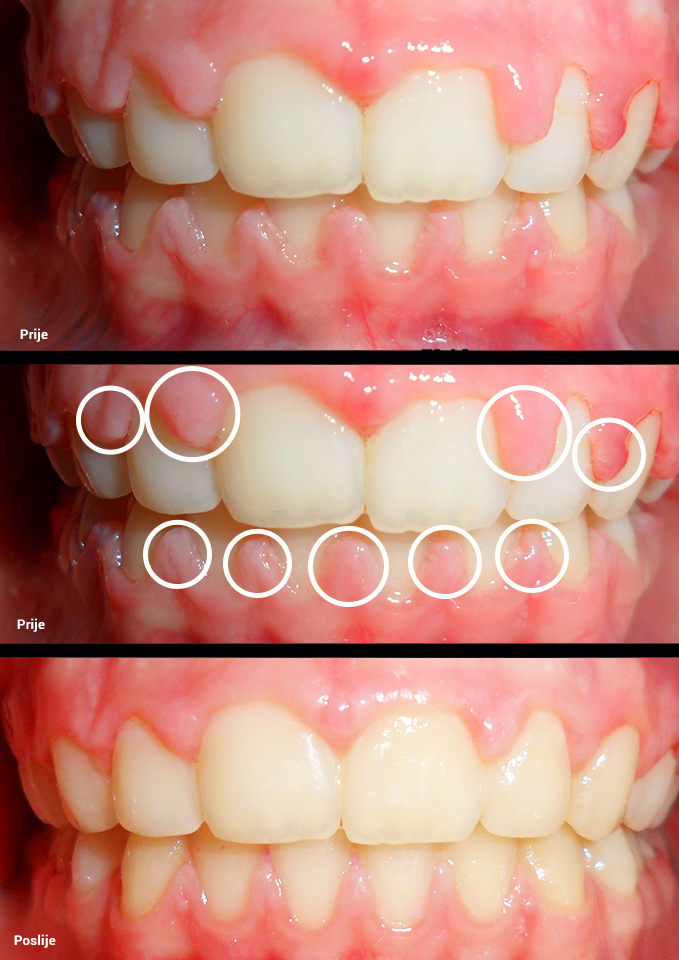

O našoj kvaliteti najbolje govore naši rezultati!

Centar za ortodonciju Petra Džapo